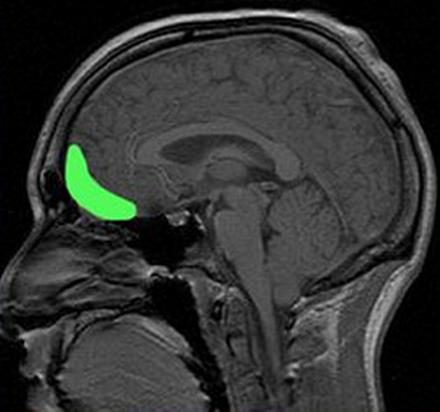

Наряду с гиперактивностью нейронов миндалевидного тела, у раздражительных людей наблюдается пониженная активность нейронов префронтальной коры (передней части лобных долей), а эта зона, между прочим, отвечает за механизмы подавления агрессии – контроль эмоциональных и поведенческих реакций.

Когда активность лобных долей подавлена, а миндалевидное тело возбуждено, любой слабый раздражитель вызывает бурную реакцию. О вреде этой реакции мы рассказали, но пока так и не ответили на главный вопрос – что делать?